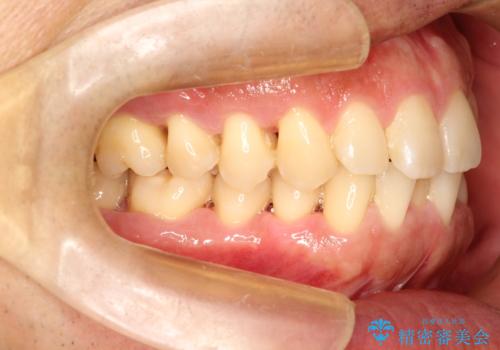

ワイヤーによる全体的ながたつきの矯正治療

- 30代男性

- メタル

- 1年3ヶ月

- 全体的ながたつきを治したいとのことで来院されました。

ワイヤー矯正とマウスピース矯正の二つの器具での治療をご案内し、ワイヤー矯正を選択されました。

インビザラインを装着するのがめんどうなので、ワイヤーの方があっているとのことで今回の治療方法を選択されました。